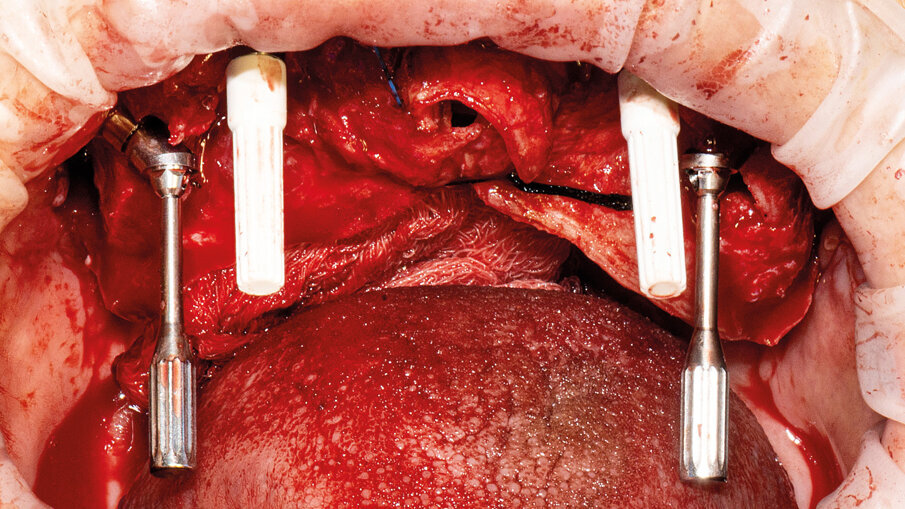

È presentata una riabilitazione con 4 impianti zigomatici (QUAD) in paziente con grave atrofia del mascellare. In questo caso la protesi con carico funzionale è stata consegnata alla paziente dopo 72 ore. Nelle immagini 1-4 viene mostrata la stereolitografia e la TC della paziente, mentre nelle immagini 5-7 viene mostrata la situazione iniziale e finale della paziente.

È stato applicato il protocollo ZAPA Zygomatic Anatomical Prosthetic Approach che definisce una successione di sequenze operative, convalidate da oltre 10 anni di chirurgia zigomatica, muovendo da un approccio protesico della riabilitazione:

- inserimento, affossamento e orientamento dell’impianto in funzione del progetto protesico (Figg. 8, 9);

- misurazione dell’altezza e angolazione del moncone con apposito strumento (Fig. 9);

- inserimento dei monconi protesici nei 4 impianti collocati – 2 standard e 2 zigomatici – e controllo della loro congruità mediante mascherina chirurgica (Figg. 10, 11).